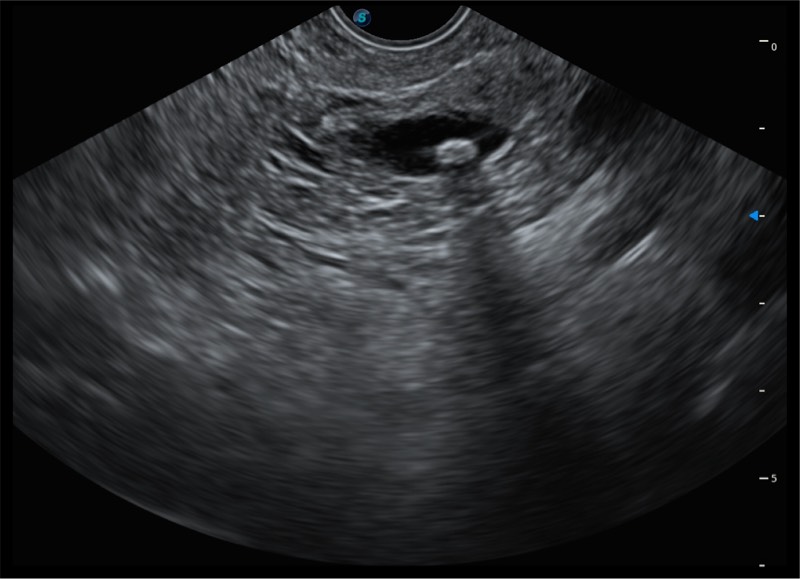

搭载百万级CMOS成像技术

及自主研发凸阵换能器,

可呈现优质的内镜和超声画面

基于二十年的超声技术积累,云顶集团官网提供了最新一代的独立超声主机,在提供高质量图像的同时满足多学科使用。具备常见多普勒技术并提供弹性成像、声学造影等高端影像技术。新一代传感器具有更强的抗干扰能力并减少图像伪影。

150°超声扫描角度

4-12MHZ宽频输出